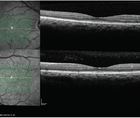

For long-term monitoring of DED, osmolarity is a good marker for therapy (Figure 2). For example, patients who were started on cyclosporine could experience the osmolarity drop after a certain amount of time. When the patient was taken off, the osmolarity went back up.3 The same applies with diverse therapies such as Omega-3s4 and compounded hormonal therapies. Osmolarity is a strong biomarker for long-term DED testing and monitoring. It may be that a patient is placed on a treatment plan that doesn’t work. If osmolarity doesn’t fall, it gives us the information and confidence that we need to try a different treatment strategy.

This makes the argument for suggesting alternative treatment plans based on data rather than a gut feeling based on previous patient outcomes. For example, if recommending an amniotic membrane, or punctal occlusion, the patient may have more confidence if you’re able to demonstrate that his or her osmolarity hasn’t fallen with previous treatment plans. He or she may be more reluctant to undergo that regimen. Now you have more objective evidence to show which treatments aren’t working and the confidence to suggest a new treatment strategy.